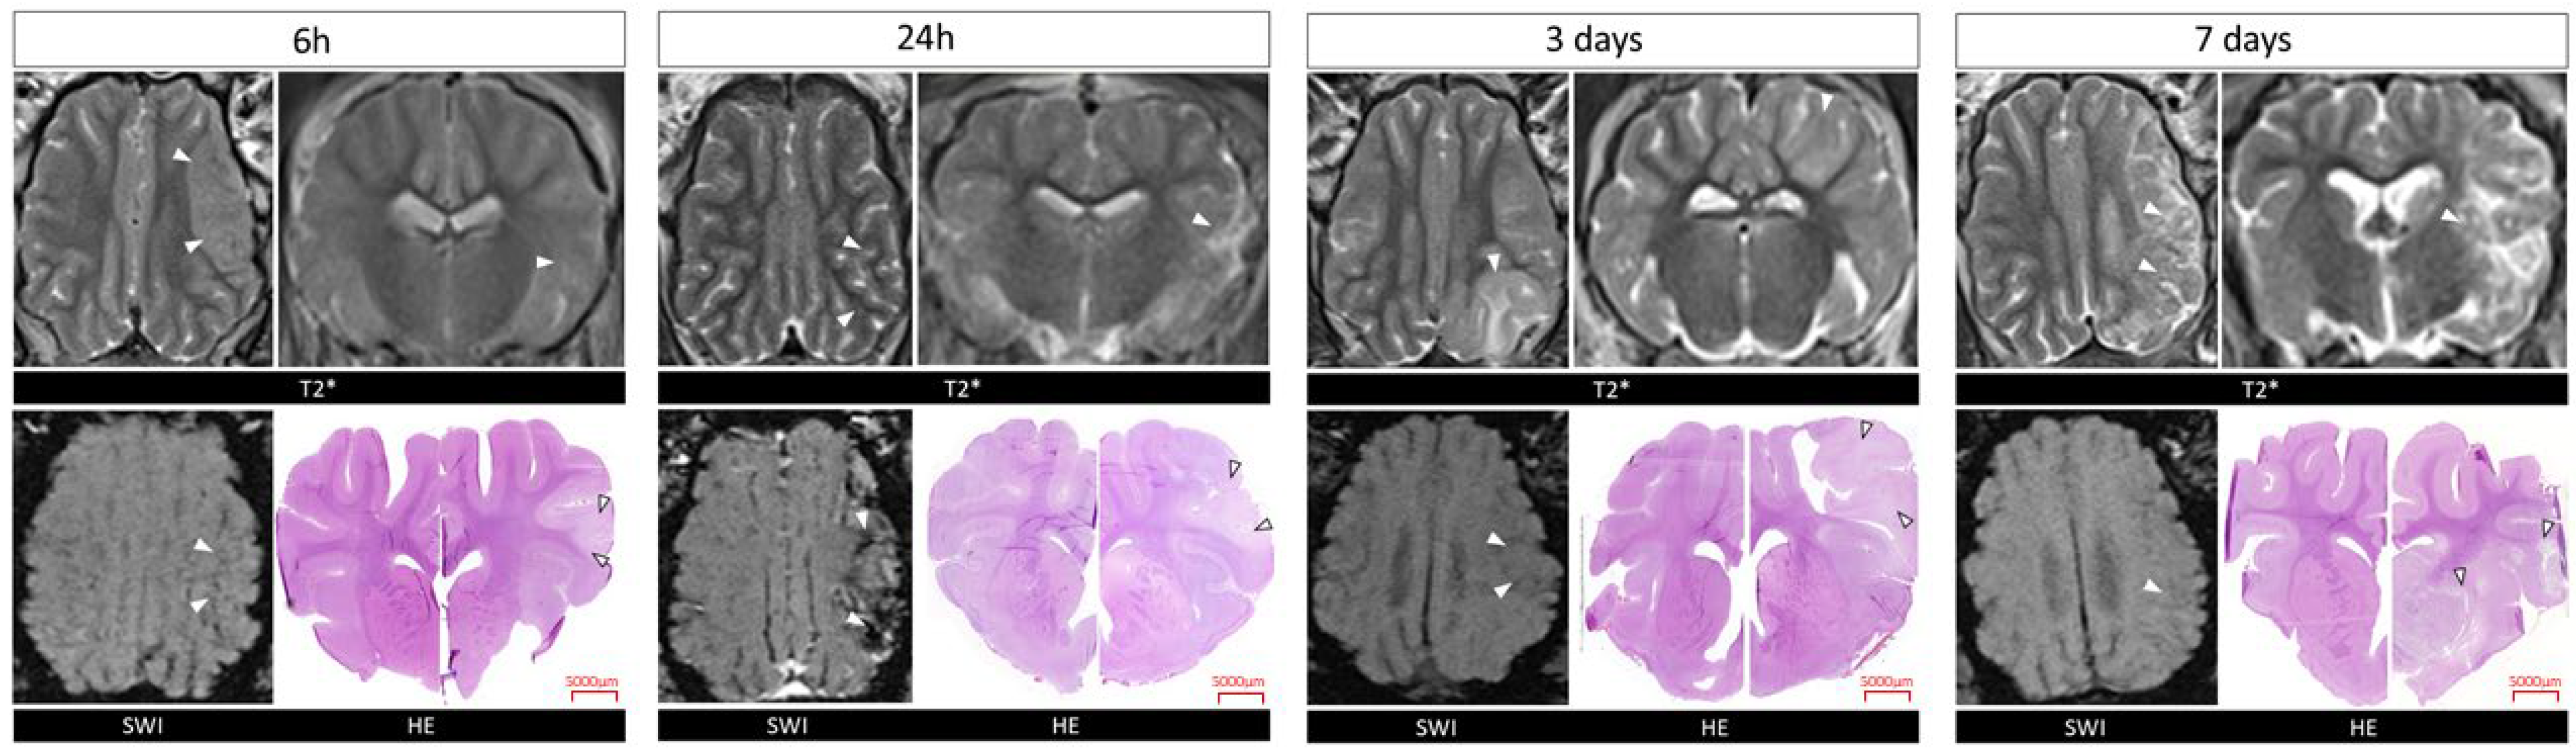

2.1. Confirmation of Ischemic Stroke Induction